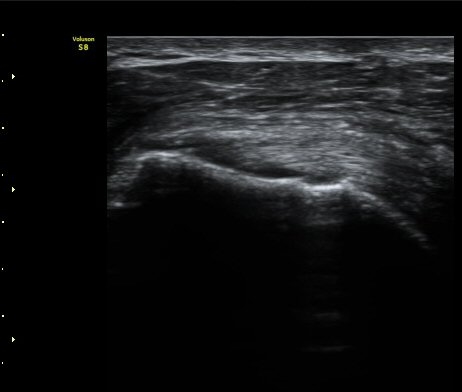

°ß°©ÇÏ±Ù°Ç Á¾´Ü¸é°Ë»ç¿¡¼­ ÀÌ»ó ¼Ò°ßÀ» º¸ÀÌÁö ¾Ê´Â´Ù(»çÁø 2)